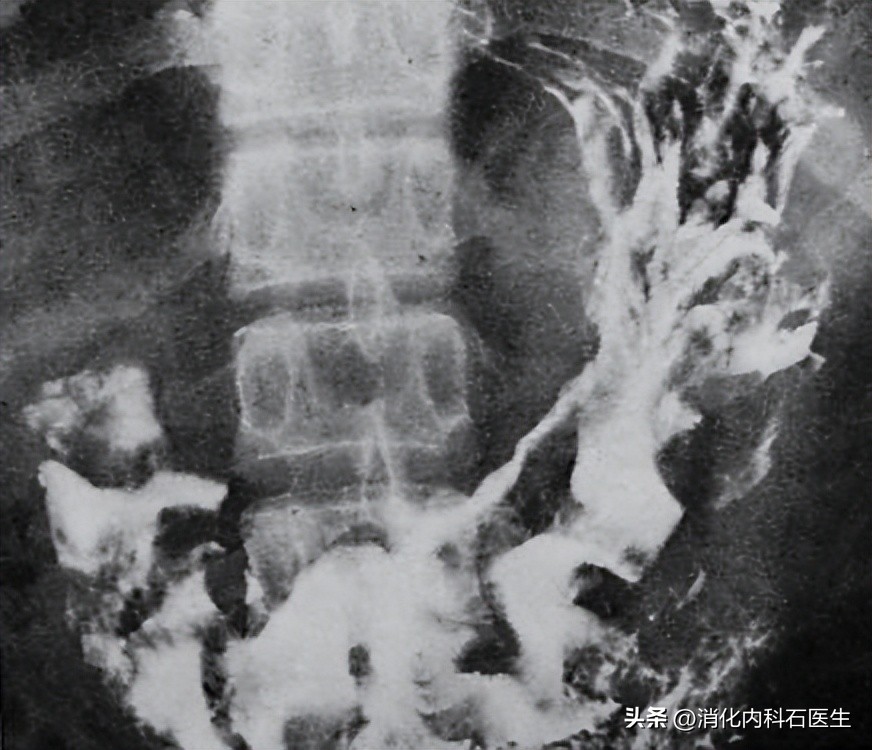

第二,一旦出现不舒服,尽量不要做钡餐。

钡餐透视,误诊率很高

钡餐检查检查胃已经逐渐被淘汰!

原因一:

钡餐检查对于早期胃癌、小胃癌、平坦性的胃癌等识别率很低,很容易漏诊和误诊。

原因二:

钡剂是一种很黏稠的物质,胃肠道排空需要很长的时间,尤其时存在便秘的患者。

服用钡餐后,如果需要做腹部CT等检查,很容易延误最佳检查时机。